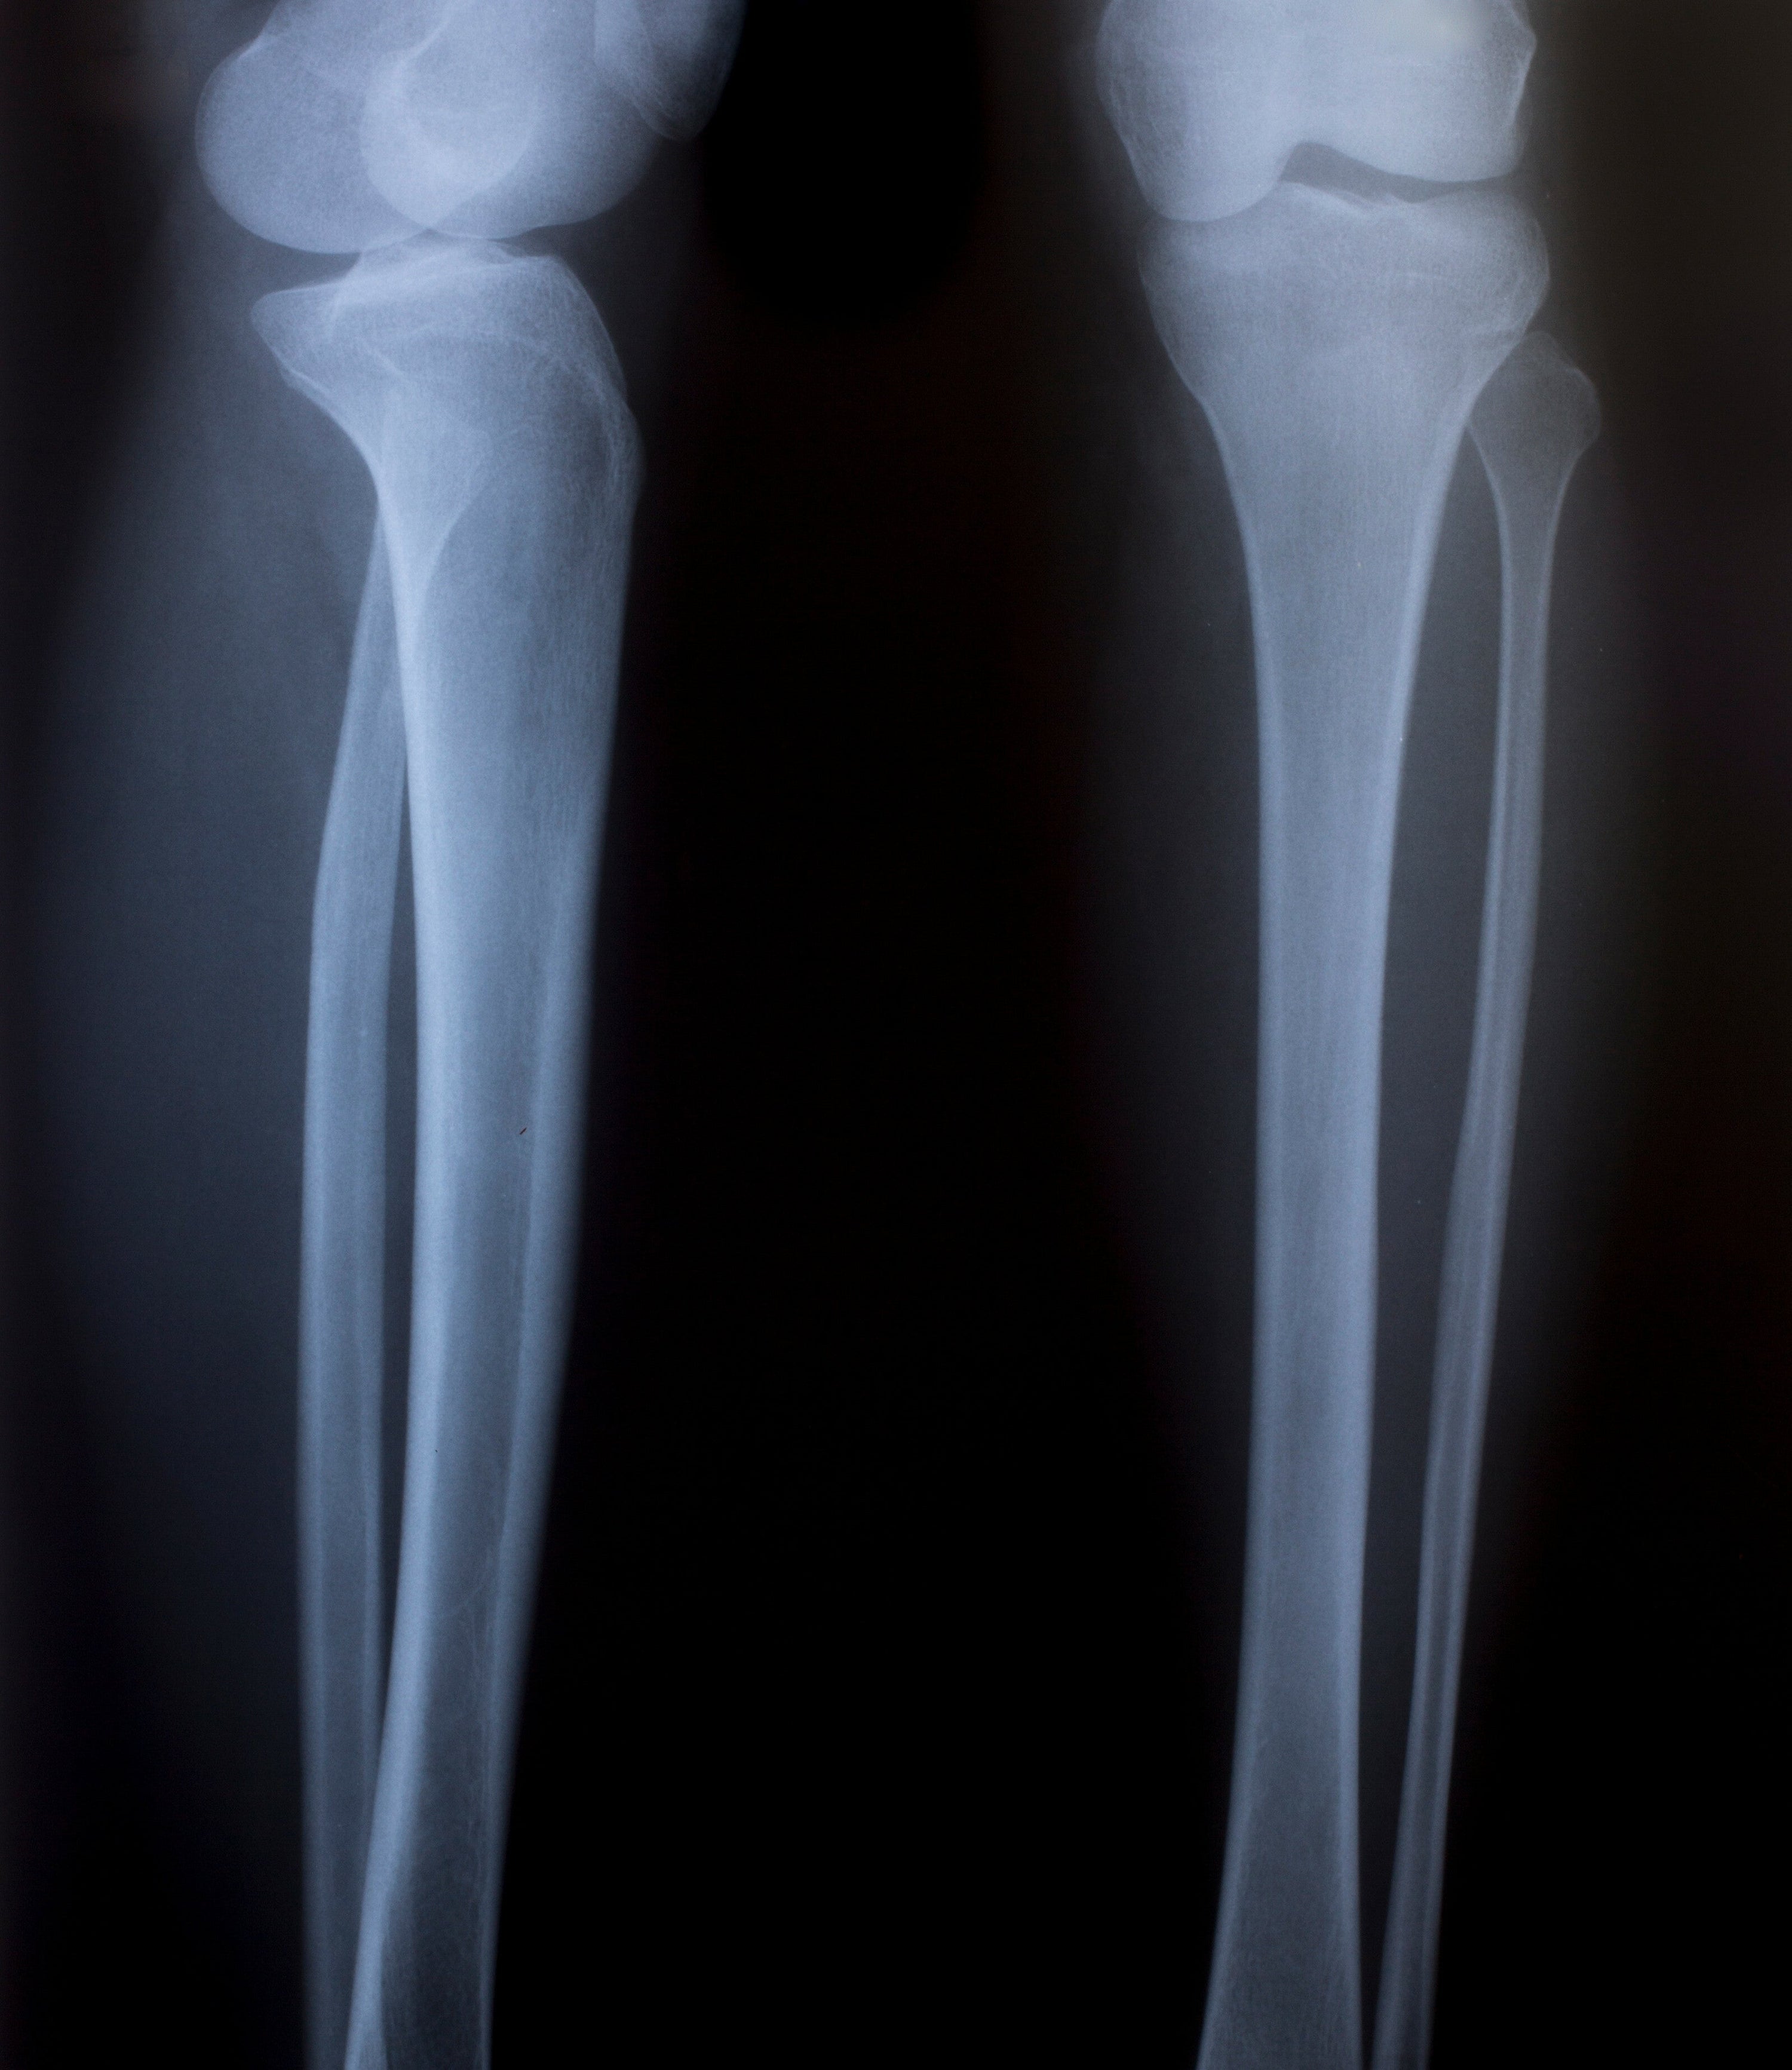

The femur, or thigh bone, is the longest and strongest bone in your body. It extends from the hip joint to the knee joint, forming the main part of your leg skeleton. Compared to other large bones, such as the tibia or the humerus, the femur stands out for its length and strength. The average femur measures about 50 cm and can withstand a weight of up to 1,000 kg.

Anatomically, the femur is divided into three main parts. The first part is the shaft. Additionally, there are the proximal (closer to the body) and distal (farther from the body) sections. The proximal section includes the femoral head, which fits into the hip joint, and the greater trochanter, where important muscle attachments are located. The shaft of the femur is slightly curved to better distribute the load. The distal section includes the knee joint, the kneecap, and the tibia.